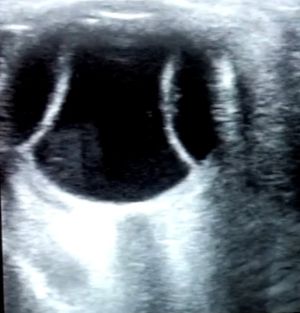

There are no specific imaging findings for SLCS, rather, imaging may show varying degrees of edema of affected organs- from pulmonary edema to pericardial effusions to intestinal edema. When SCLS affects the eye, the patient may have choroidal effusions, which can be seen on neuro-imaging and ophthalmic ultrasonography (Figure 1).